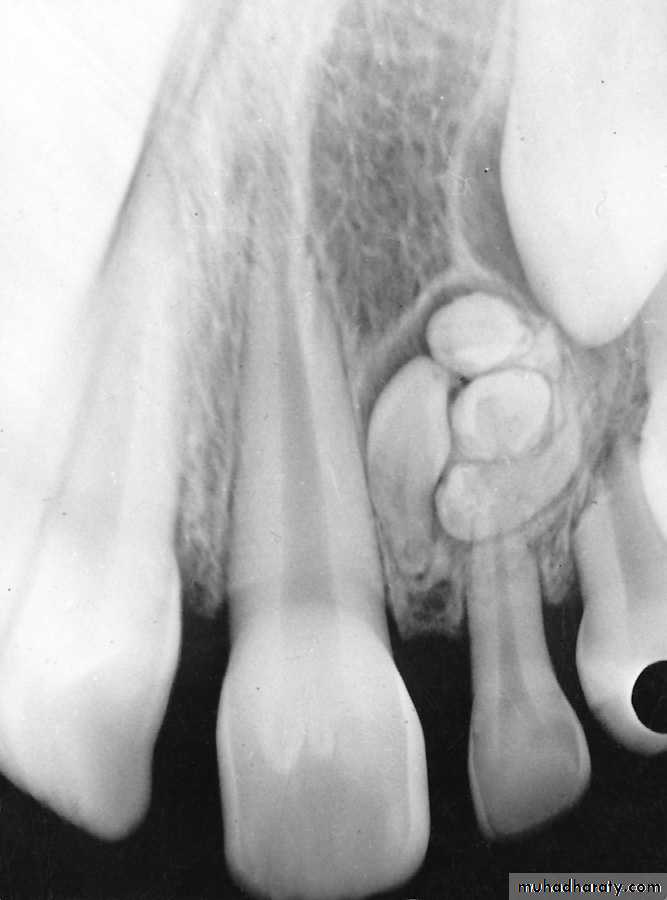

Odontoma

Necrotic tooth resulting from a carious exposure of the pulp of the second primary molar. Because the succedaneous second premolar was congenitally missing, a decision was made to attempt to save thetooth as a functional space maintainer through the growing years, if possible. Note the evidence of internal resorption

at the floor of the pulp chamber.

Ankylosis of the primary teeth which prevents the eruption of the second permanent premolar